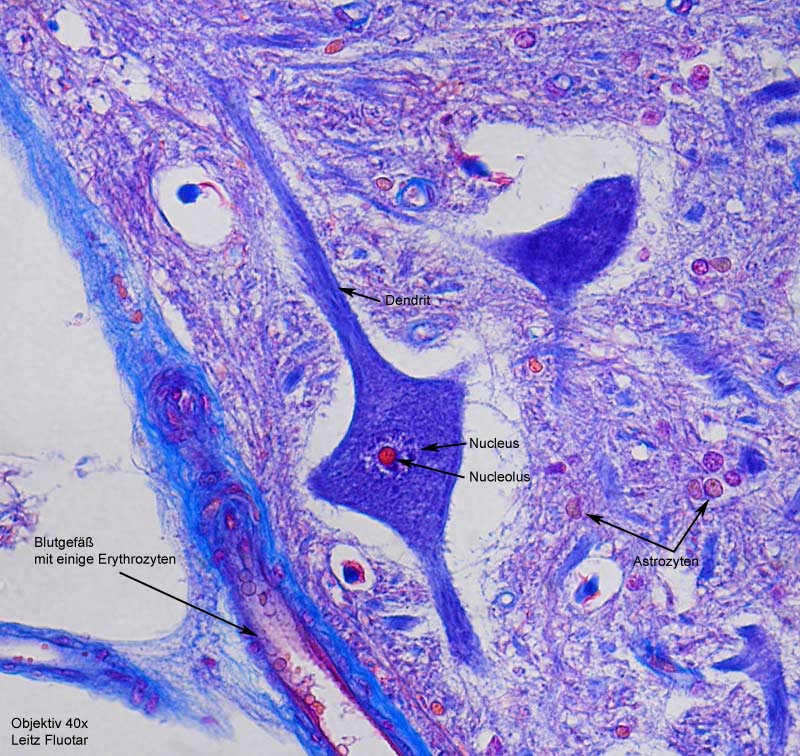

Histologie des Rückenmarks eines Rindes

Histologie des Rückenmarks eines Rindes.

Kerne intensiv rot, Collagenes Bindegewebe blau, Erythrocyten orange, Gliafasern rot, Protoplasma und Muskulatur rotorange gefärbt.

Aufnahmen sind gemacht mit ein Coolpix 4500 mit ein 10x Leitz Periplan Brille Okular.

Objektive von Leitz 2,5x Achromat, 10x, 16x, 40x und 100x Fluotar.